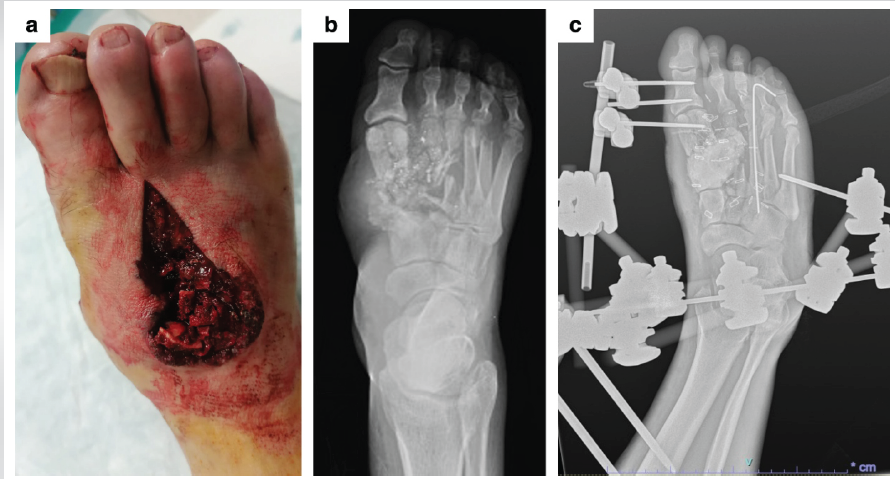

Figure 4: Initial presentation in Case 2. (a) Dorsal soft-tissue defect of the foot. (b) Initial X-rays at admission. (c) X-rays after surgical debridement and stabilization with an external fixator and Kirschner wire.

A 67-year-old male hunter was admitted to Sant’Anna Hospital in Como with a composite right foot injury sustained during a boar hunting accident at close range (50 cm) involving a high-velocity rifle projectile. The soft-tissue defect measured 25 cm2 dorsally and 24 cm2 plantarly. Radiological evaluation revealed loss of the base and diaphysis of the first metatarsal, fracture of the first metatarsal head, loss of the base and diaphysis of the second metatarsal, fractures of the third and fourth metatarsals, and fracture of the proximal phalanx of the third toe. CT angiography demonstrated patency of the posterior tibial, anterior tibial, and peroneal arteries, with interruption of the dorsalis pedis artery at the base of the second metatarsal. An antibiotic regimen (amoxicillin, gentamicin, and metronidazole) was initiated immediately. Urgent debridement was performed, with removal of devitalized bone fragments from the first and second rays. Osteosynthesis of the third metatarsal was achieved using an intramedullary K-wire, and stabilization was provided with a Hoffmann 3 (Stryker) external fixator spanning from the distal tibia to the calcaneal tuberosity and the fifth metatarsal (Fig. 4).